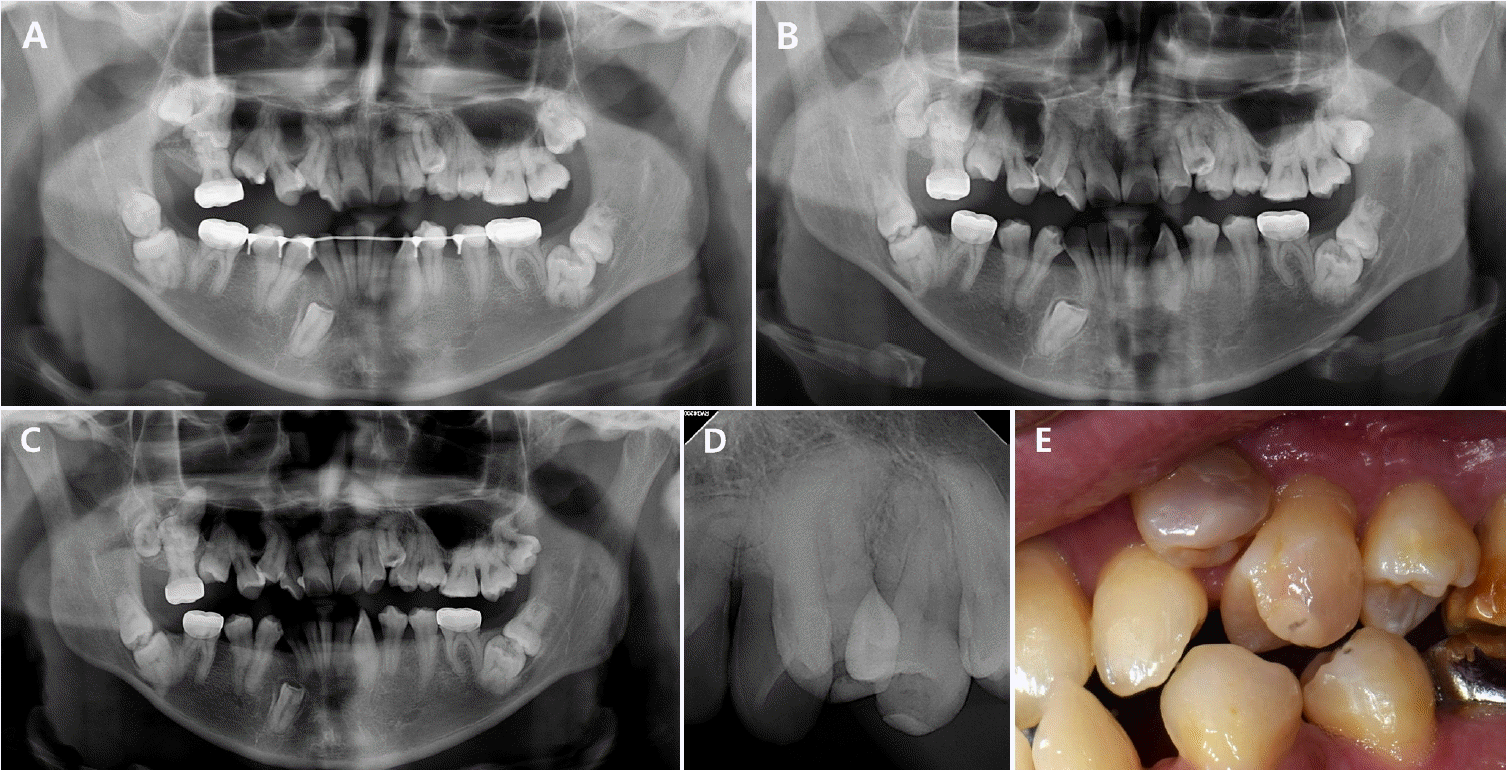

7세 남아가 교정 치료를 주소로 조선대학교 치과병원 소아 치과에 내원하였다. 방사선학적 검사 상 발육 중인 상악 좌측 견치 치배의 교두정에서 방사선 투과상이 발견되었으며, 별다른 임상 증상은 존재하지 않았다(Fig. 6). 해당 병소를 PEIR으로 진단하고 경과관찰 후 수복치료를 계획하였다.추적관찰 3년째, 정기검진 시 환아의 구내에서 상악 좌측 견치의 맹출이 확인되었다. 임상 및 방사선학적 검사 결과, 견치 교두정을 중심으로 한 흡수성 와동이 관찰되었다(Fig. 7). 환아는 자각 증상을 호소하지 않았고, 타진 검사에서 음성 반응을 보였으며, 전기 치수 반응 검사(Gentle-pulse, Parkell, Edgewood, NY, USA) 시행 시 3에서 양성 반응을 나타내었다. 방사선학적 검사 상 치수와의 근접성을 고려하여 치수 복조술을 동반한 수복 치료를 시행하기로 하였다.치료 시 병소의 입구를 넓히고 병변 부위를 제거한 후, 간접 치수복조술을 시행하였다. 칼슘 실리케이트 계열의 복조재인 TheraCal PT (BISCO, Schaumburg, IL, USA)를 적용한 후 GI 베이스(Fuji IX GP, GC Corp., Tokyo, Japan)를 이장하고, 접착제(Scotchbond Universal Adhesive, Solventum, St. Paul, MN, USA)를 도포한 후 복합레진(Filtek Z250 Universal Restorative A2, Solventum, St. Paul, MN, USA)으로 충전하였다(Figs. 8A-C). 일주일 뒤 재내원 시 시행한 임상 및 방사선학적 검사에서 특이 소견은 관찰되지 않았다(Fig. 8D).

Figure 7.

Preoperative clinical and radiographic images. A. A white discoloration is noted on the cusp tip of tooth #23. B. Clinical view from the occlusal aspect shows a resorptive lesion centered on the cusp tip. C. Periapical radiograph.

Figure 8.

Clinical photographs during treatment. A. The cavity entrance is enlarged. B. After application of TheraCal PT. C. After completion of resin restoration. D. Postoperative periapical radiograph.